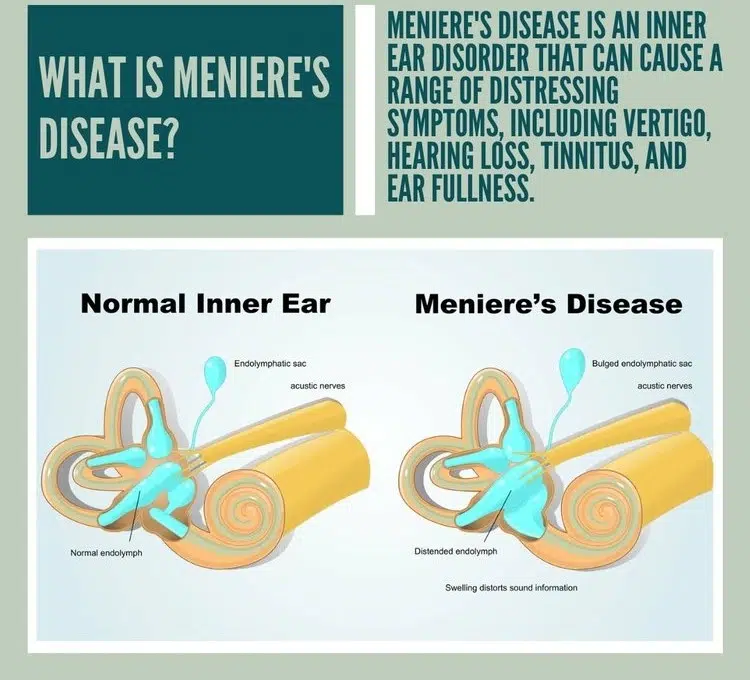

Understanding Meniere’s Disease – Symptoms, Stages, Treatment & More Image Source: .brisbanephysiotherapy.com Ménière’s disease